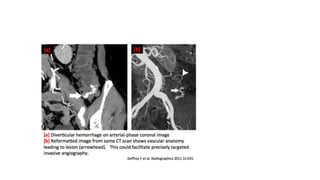

COMPUTED TOMOGRAPHY

• Triple phase helical CT scanning using IV contrast is safe, fast convenient

and accurate diagnostic tool

• Criteria for identification include :

• vascular dilatations, vascular extravasation, spontaneous hyper density of

the peribowel fat

• Presence of diverticula - this alone is not enough for localization

• Comparable identification rate to mesenteric angiography and colonoscopy

CT- ANGIOGRAM

• This is different from CT with intravenous contrast

• Cost effective accurate and rapid tool in the diagnosis of acute LGIB

• Studies report a pooled sensitivity of 85.2%- 89% and a specificity of 74%-

96.9% and positive predictive value of 98.5%

• When combined with visceral arteriography it increases diagnostic and

localization yield- jacovides et al

• Can track vessel and identify exact bleeding vessel

• Requires bleeding at 0.3 - 0.5 ml/min